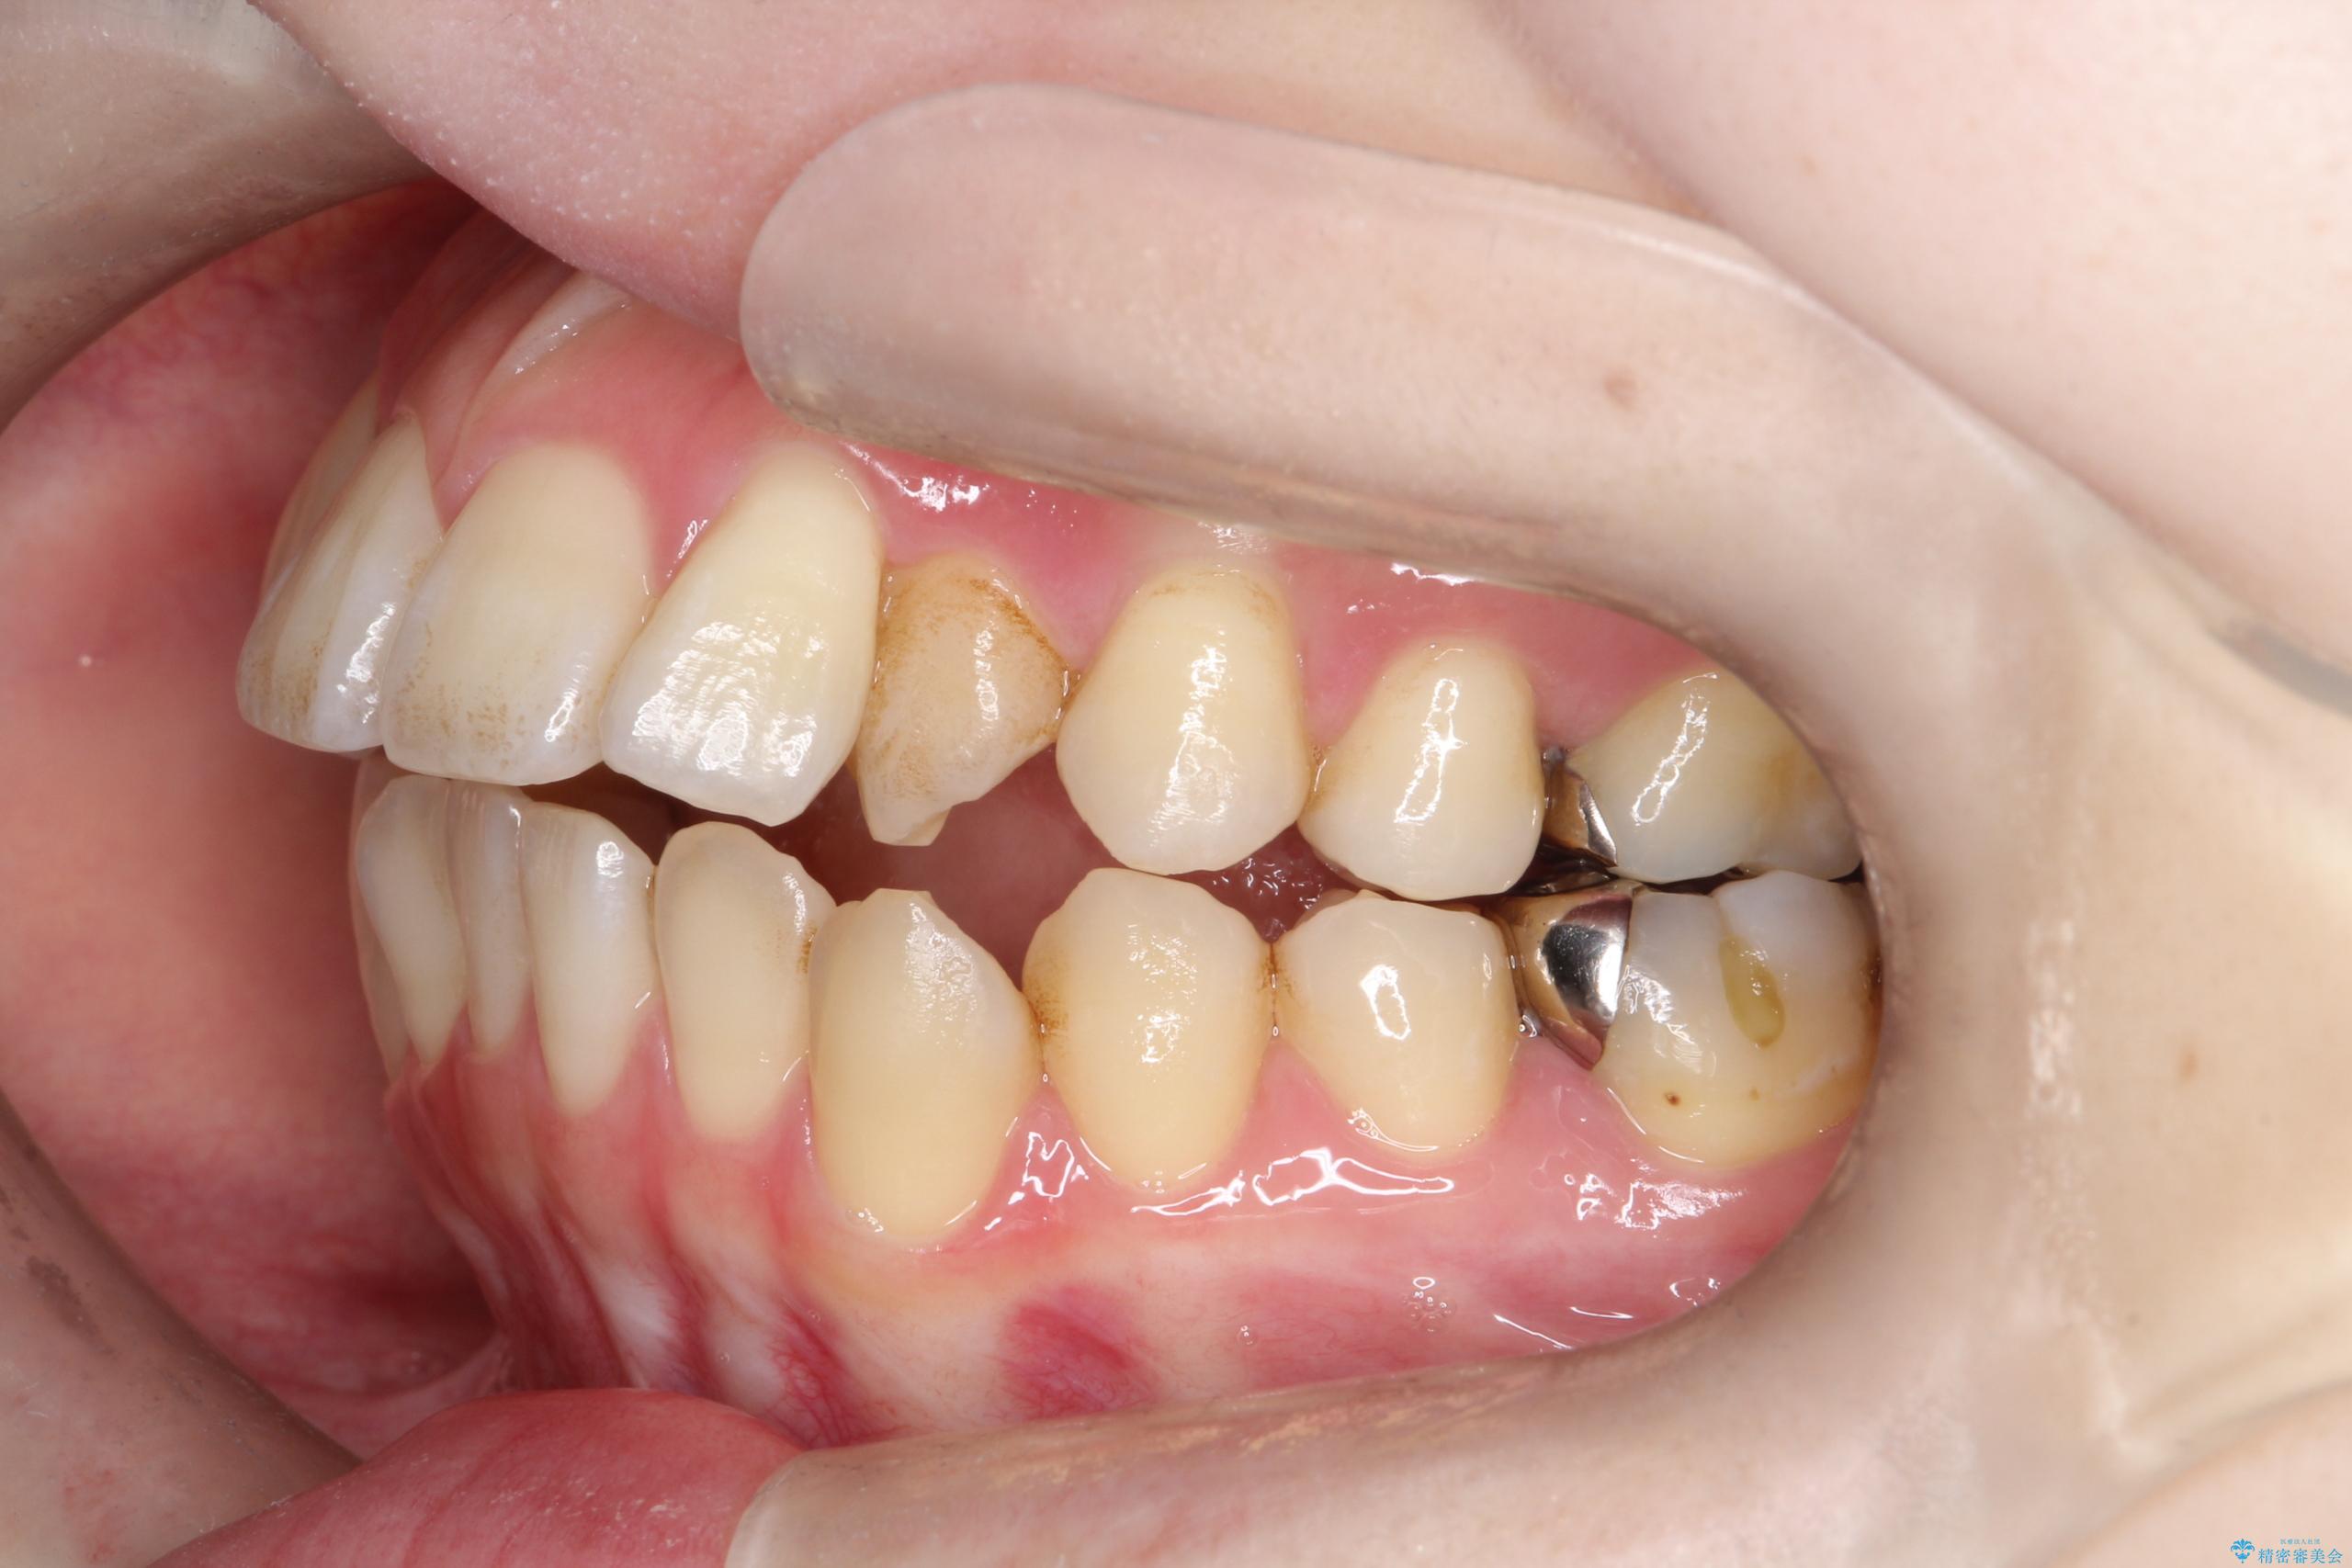

- 開咬と歯のデコボコ(叢生)、八重歯を主訴にご来院された患者様です。

矯正の精密検査の結果、上顎左右4番および下顎左右5番の計4本を抜歯し、ワイヤー矯正(クリア装置)にて治療を行いました。

虫歯があったので、虫歯治療は矯正前に行っています。